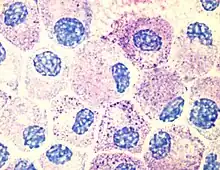

Most histamine in the body is generated in granules in mast cells and in white blood cells (leukocytes) called basophils. Mast cells are especially numerous at sites of potential injury – the nose, mouth, and feet, internal body surfaces, and blood vessels. Non-mast cell histamine is found in several tissues, including the hypothalamus region of the brain, where it functions as a neurotransmitter. Another important site of histamine storage and release is the enterochromaffin-like (ECL) cell of the stomach.

The most important pathophysiologic mechanism of mast cell and basophil histamine release is immunologic. These cells, if sensitized by IgE antibodies attached to their membranes, degranulate when exposed to the appropriate antigen. Certain amines and alkaloids, including such drugs as morphine, and curare alkaloids, can displace histamine in granules and cause its release. Antibiotics like polymyxin are also found to stimulate histamine release.

Mast cells serve an important immunological role by defending the body from antigens and maintaining homeostasis in the gut microbiome. They act as an alarm to trigger inflammatory responses by the immune system. Their presence in the digestive system enables them to serve as an early barrier to pathogens entering the body. People who suffer from widespread sensitivities and allergic reactions may have mast cell activation syndrome (MCAS), in which excessive amounts of histamine are released from mast cells, and cannot be properly degraded. The abnormal release of histamine can be caused by either dysfunctional internal signals from defective mast cells or by the development of clonal mast cell populations through mutations occurring in the tyrosine kinase Kit.[21] In such cases, the body may not be able to produce sufficient degradative enzymes to properly eliminate the excess histamine. Since MCAS is symptomatically characterized as such a broad disorder, it is difficult to diagnose and can be mislabeled as a variety of diseases, including irritable bowel syndrome and fibromyalgia.[21]